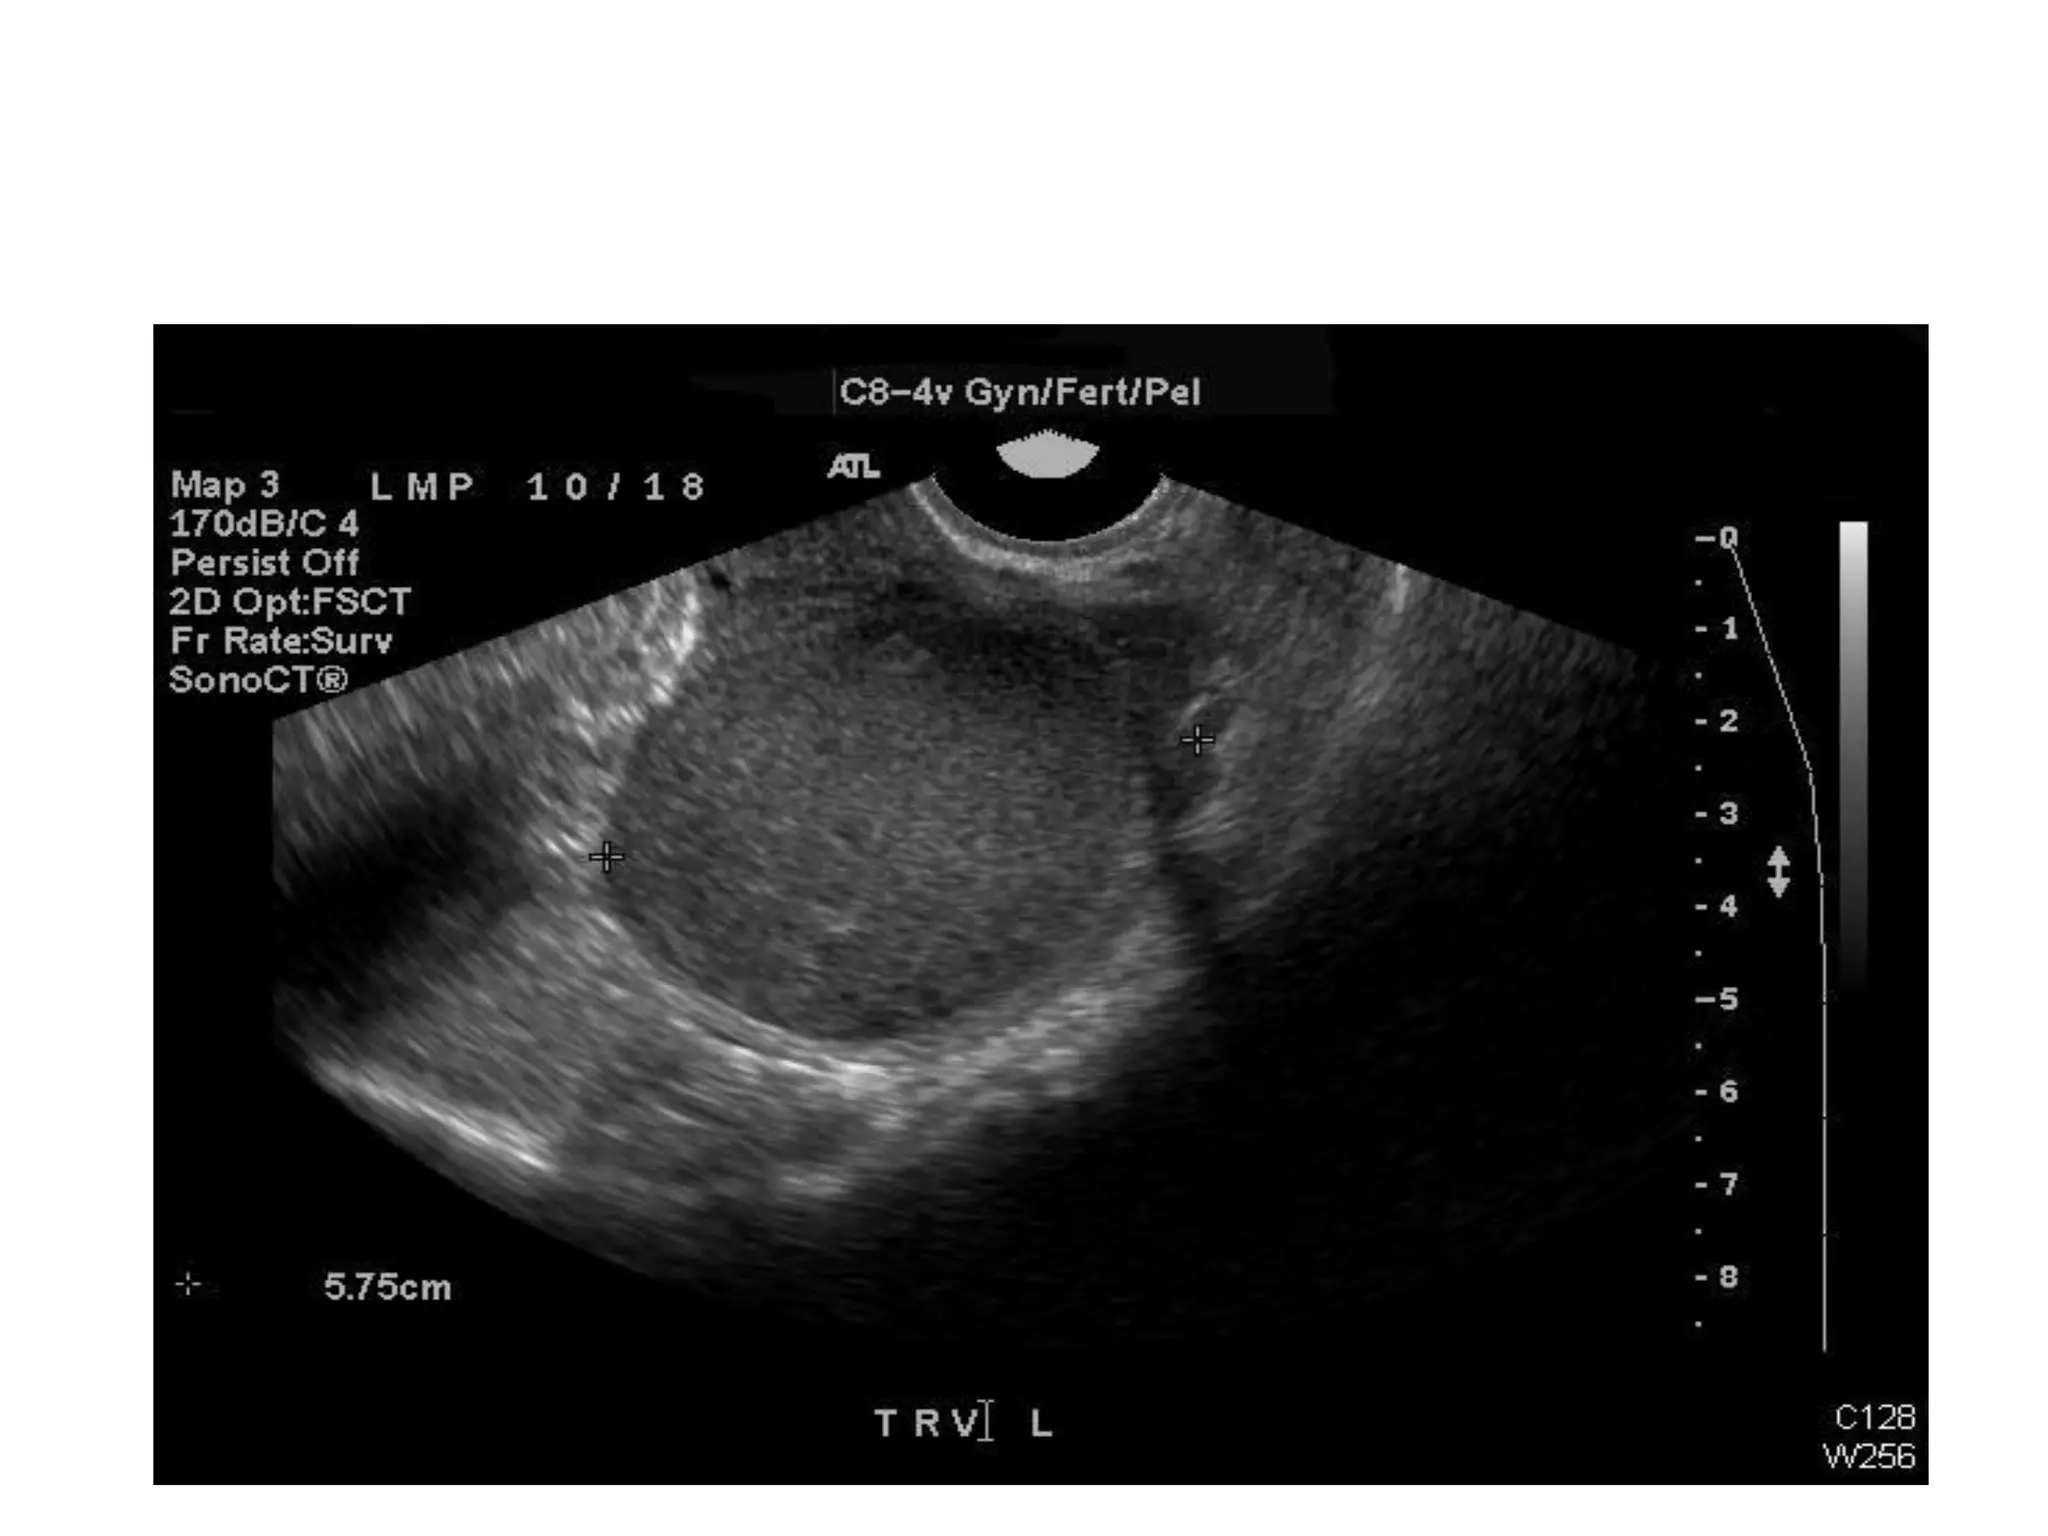

Transvaginal Ultrasound:

• Low level internal echoes

• Thick walled

• Homogeneous “ground glass” appearance

• Unilocular or Multilocular

• Often solid appearing or cystic

• Can show varying degrees echogenicity (even

anechoic) in locules with fluid levels

• Can show punctate echogenic foci (wall or central

calcification) with distal shadowing

• Round Shape

Regular Margins

Ultrasound of Endometrioma